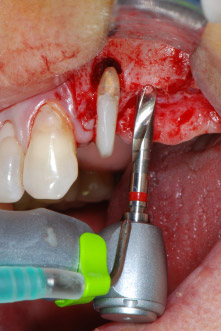

Implant beds were prepared at sites 25 and 26 with rotary instruments, used in a contra-angle handpiece with a 20 : 1 transmission ratio with an updated powerful implant motor (Implantmed, W&H) (Fig. 8).

implant motor

Fig. 8: Rotary preparation of the implant bed short of the floor of the maxillary sinus at position 25, carried out with an updated implant motor.